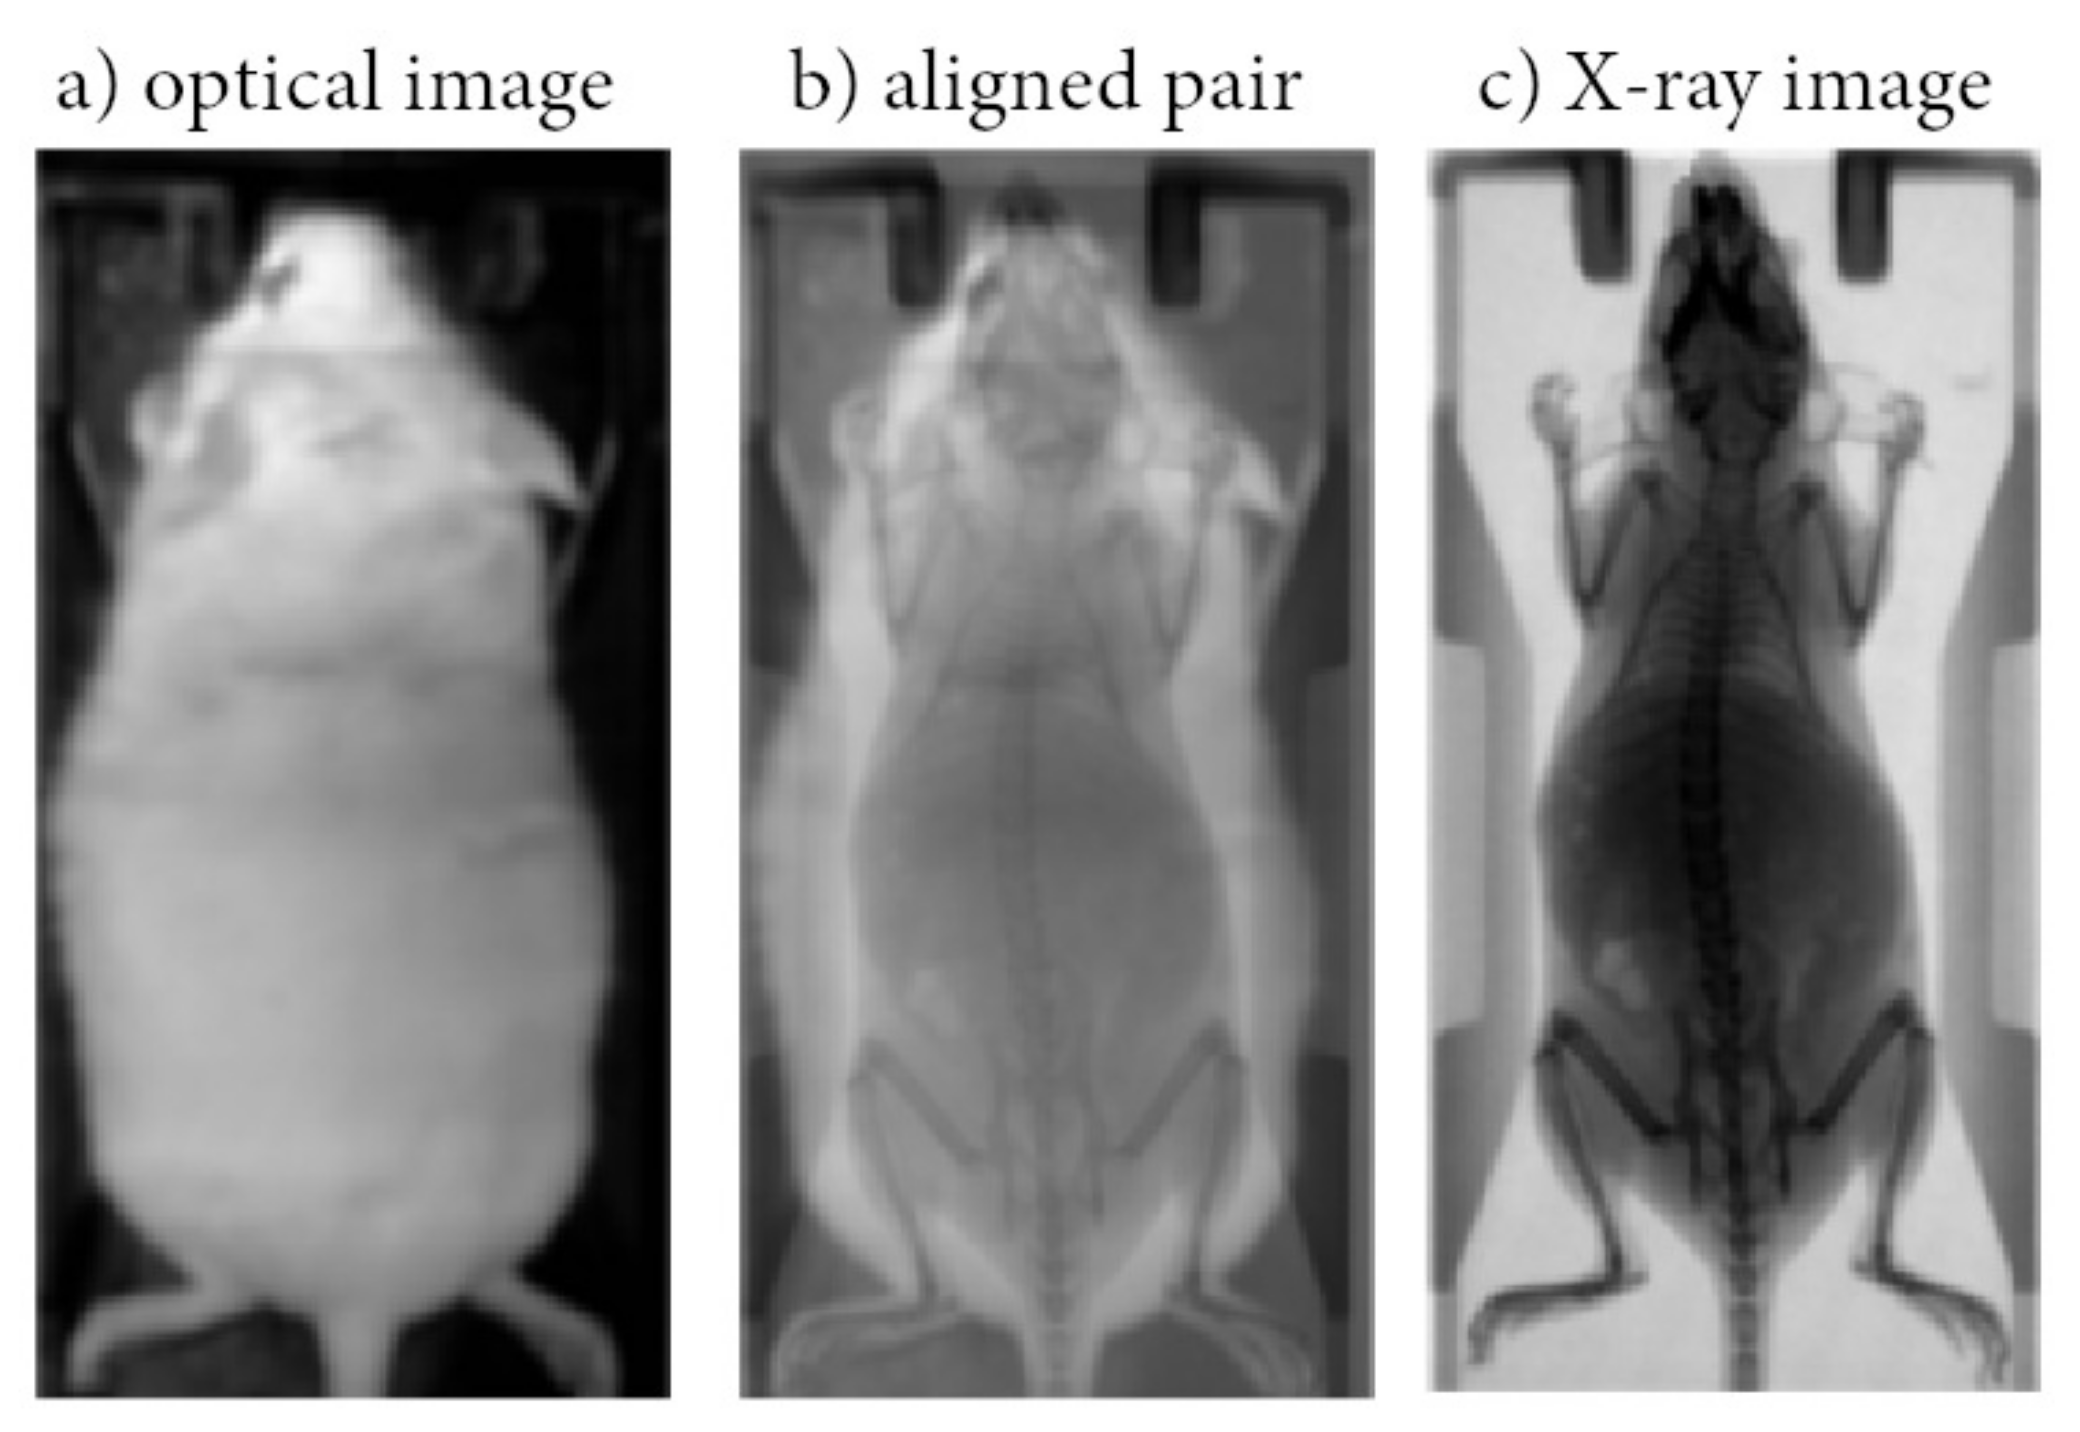

2.1. Data Collection and Preprocessing

2.2. Modeling and Performance Evaluation